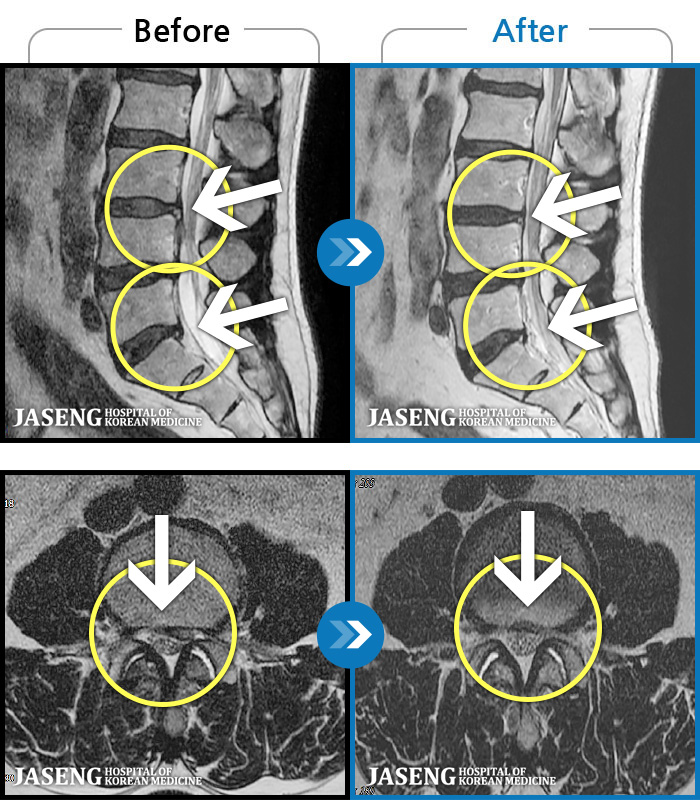

MRI ġ

1,304 MRI ũ ʸ Ȯϼ.